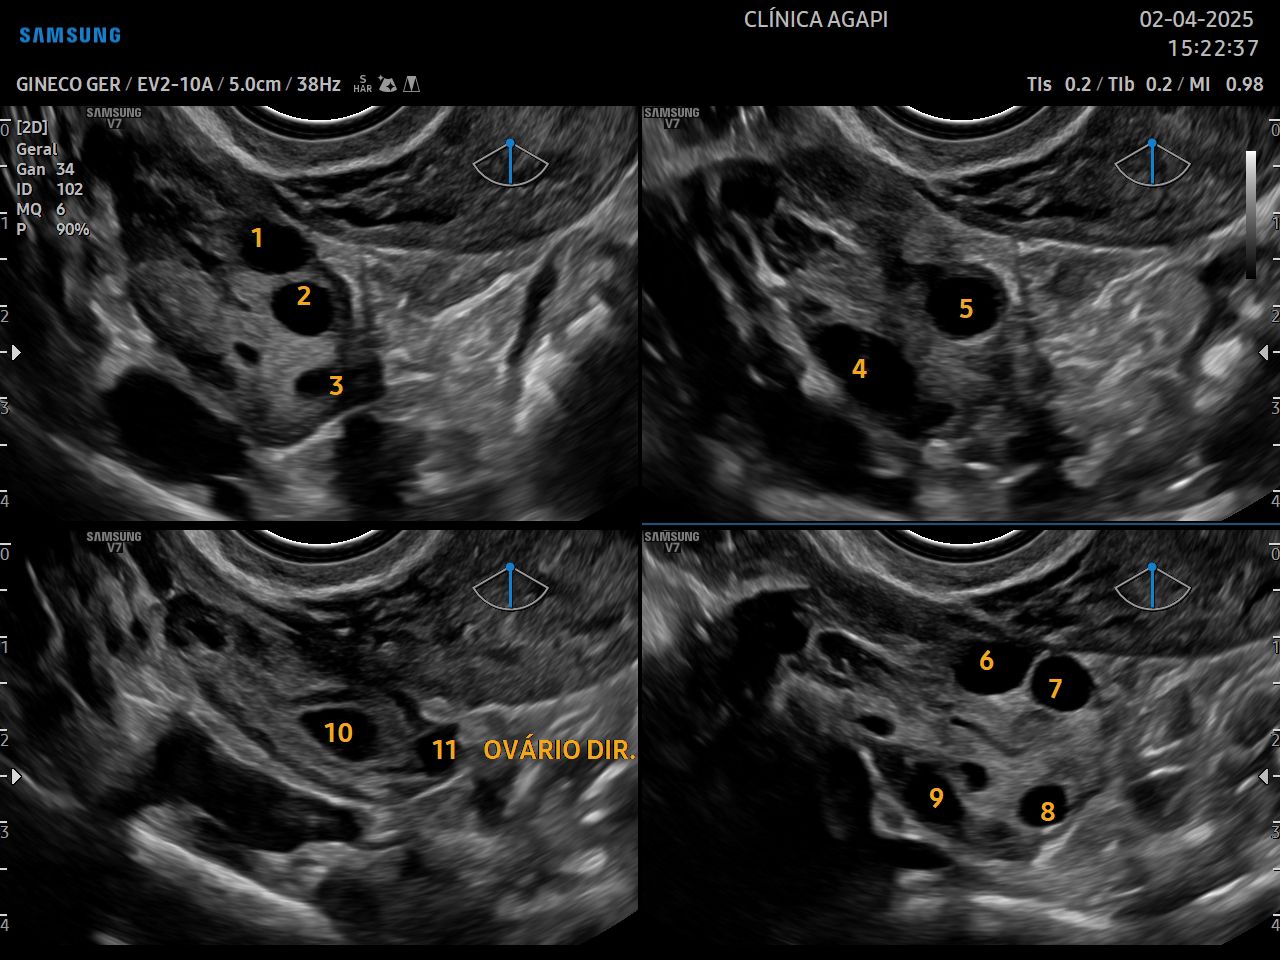

A contagem de folículos antrais é feita por meio de ultrassom transvaginal, geralmente entre os dias 2 e 5 do ciclo. O teste pode ser feito como parte de uma avaliação de fertilidade ou pode ser solicitado antes de um ciclo de tratamento de fertilidade.